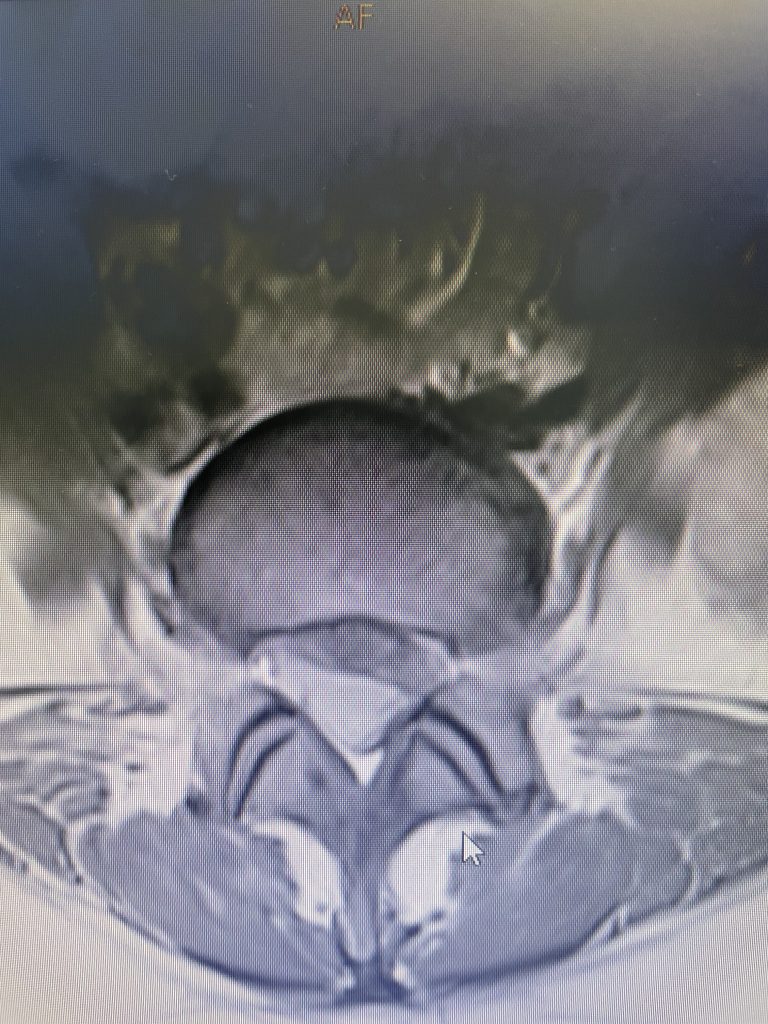

A 35-year-old female presents with severe low back pain and progressive left leg pain. She had initially presented nine months prior with mainly low back pain with mild left leg symptoms. She had an MRI (Fig 1) demonstrating a transitional L5 lumbar vertebra. This L5 vertebra is sacralized in that it is more anatomically associated with the sacral level with a rudimentary disc between it and the segment below. Because of the rudimentary disc there is very little movement at that level, hence more stress is put on the segment above.

Figure 1